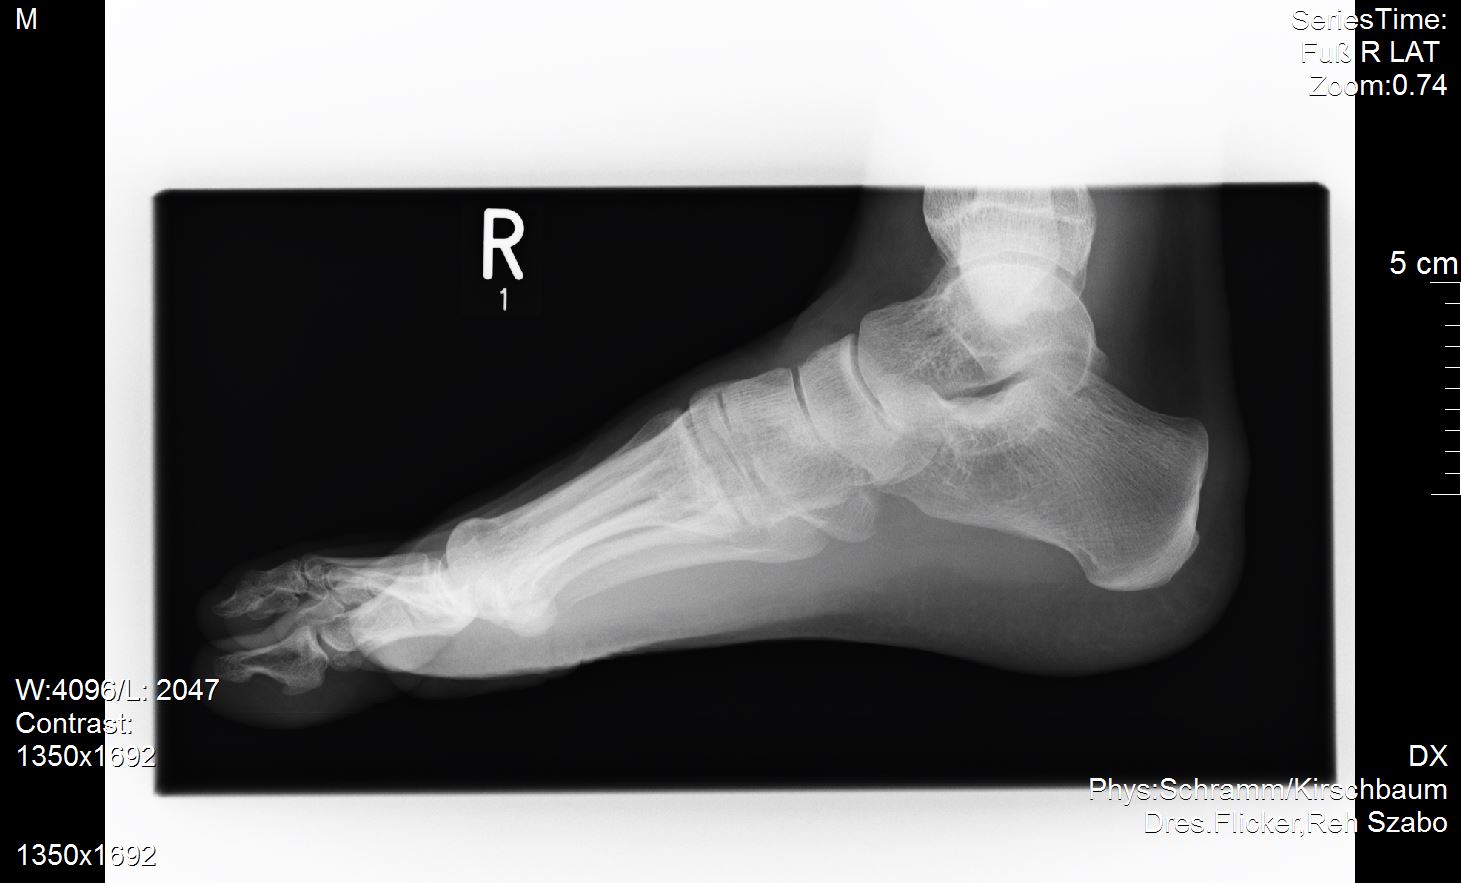

Ich versuche mal meine Röntgenbilder anzuhängen. Vielleicht ist ja ein Experte unter uns der dazu was sagen kann?

Ich habe außer dem mir diagnostizierten Spreizfuß nach oben stehende Zehen. Weiß nicht genau ob man dies Hammerzeh oder Krallenzeh nennt was ich habe aber es geht in die Richtung.